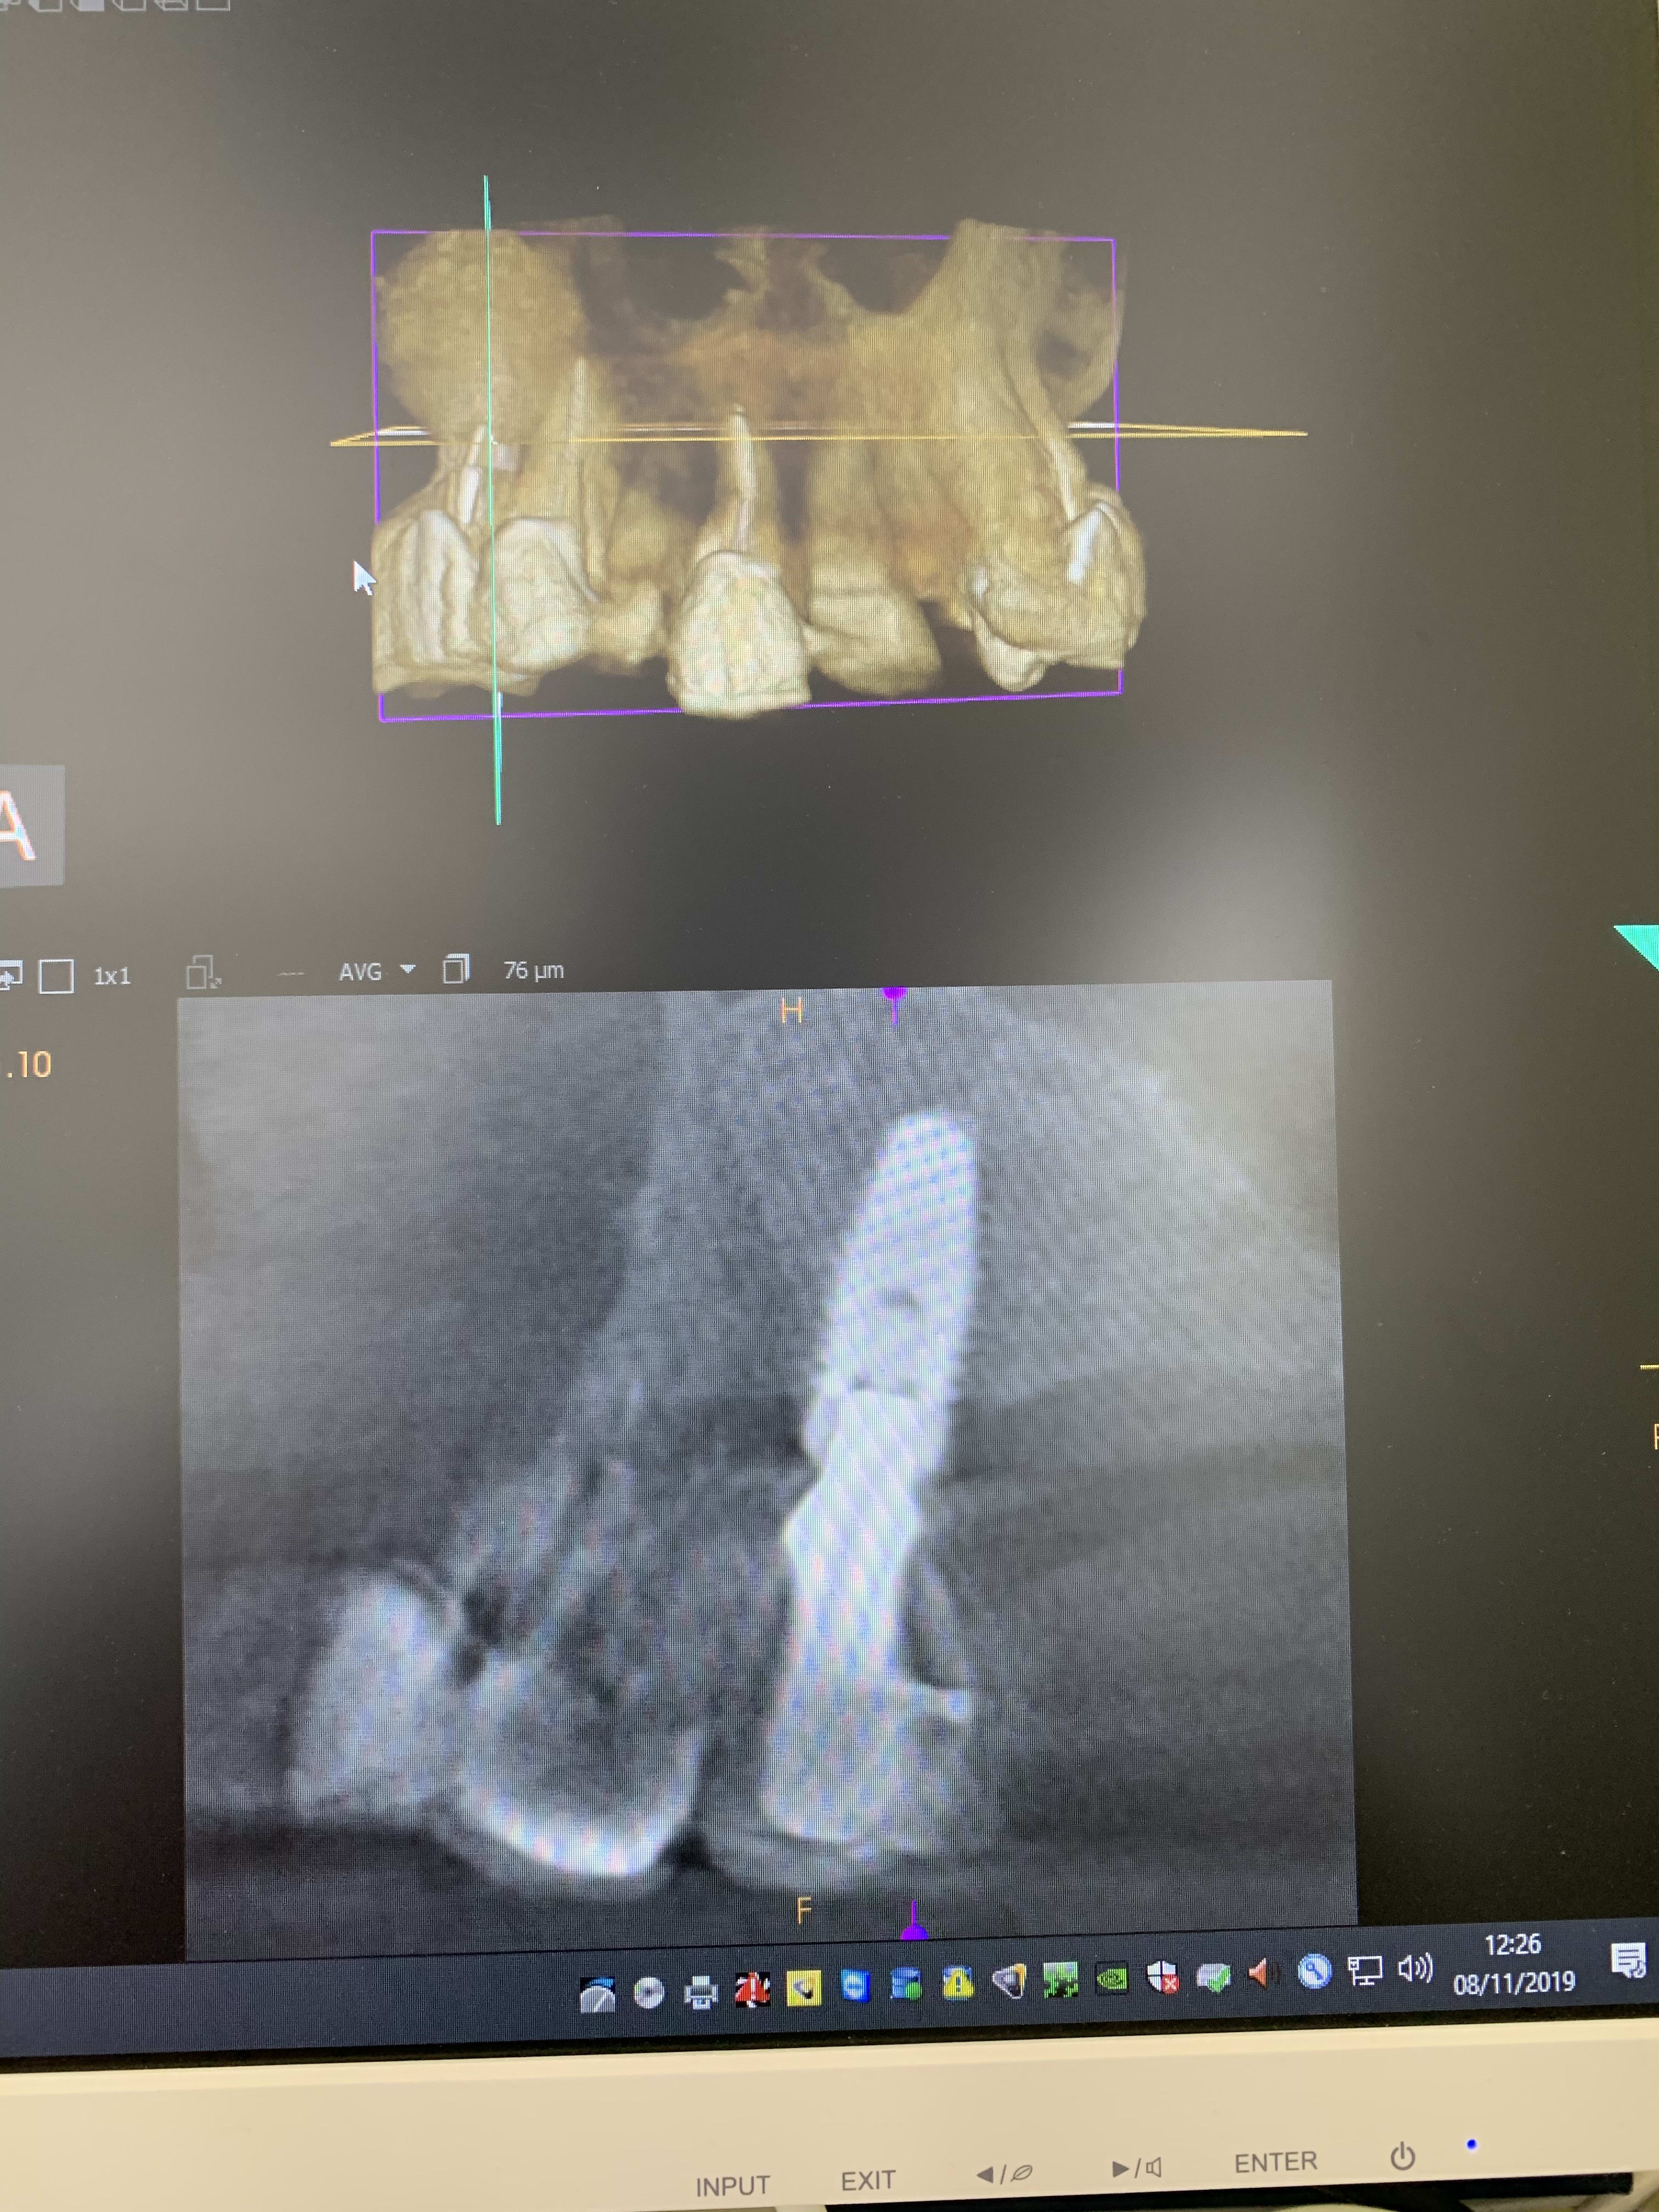

Il y a vraiment des différences de dingue entre les machines !

Les images 3 et 4, les images 6 et 7 sont prises à quelques années d’intervalles.

La machine de 2008 fait très peu d’artefacts, celle de 2018 énormément. Elle à le mar pour les « supprimer », mais ça n’arrange rien !

Les artefacts métalliques sont bien différents selon les machines.

A l’adf on me dit « regardez on voit même les spires des implants », avec ma bécanne de 2008 je vois les spires des vis dans les implants, les têtes de vis... je n’ai rien vu d’équivalent sur les machines récentes.

Les photos ne sont pas de très bonnes qualités, prises avec un 6S sans trop d’effort.

Regardez comme les tenons sont bien trop larges à la radio !

Les implants sont de gros pâtés blancs...